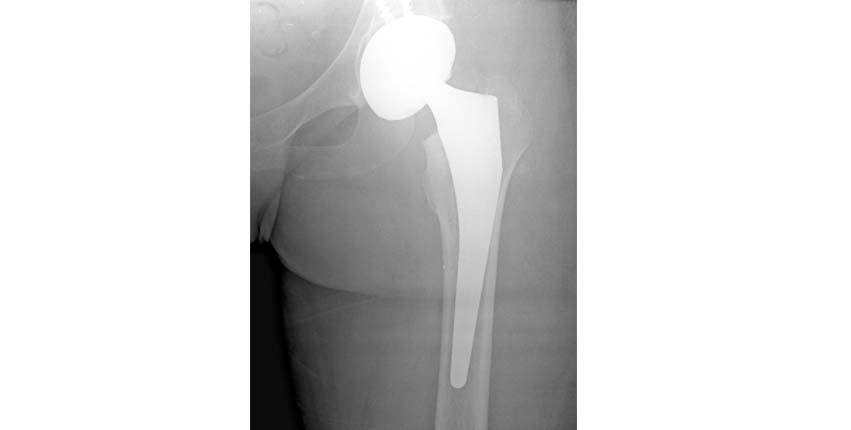

5.At this point the femoral head has been placed in the hip socket component. The hip is now "reduced" (put back in place). A final check of the position of the hip implants is performed. The leg is moved in extreme positions to be sure that the hip implants do not come apart due to dislocation. Potential reasons for the hip to dislocate would be abnormal contact between the implants, inaccurate positioning of the implants, or inadequate soft tissue (muscle) tension.

6.The final radiograph shows the implants to be in appropriate position.